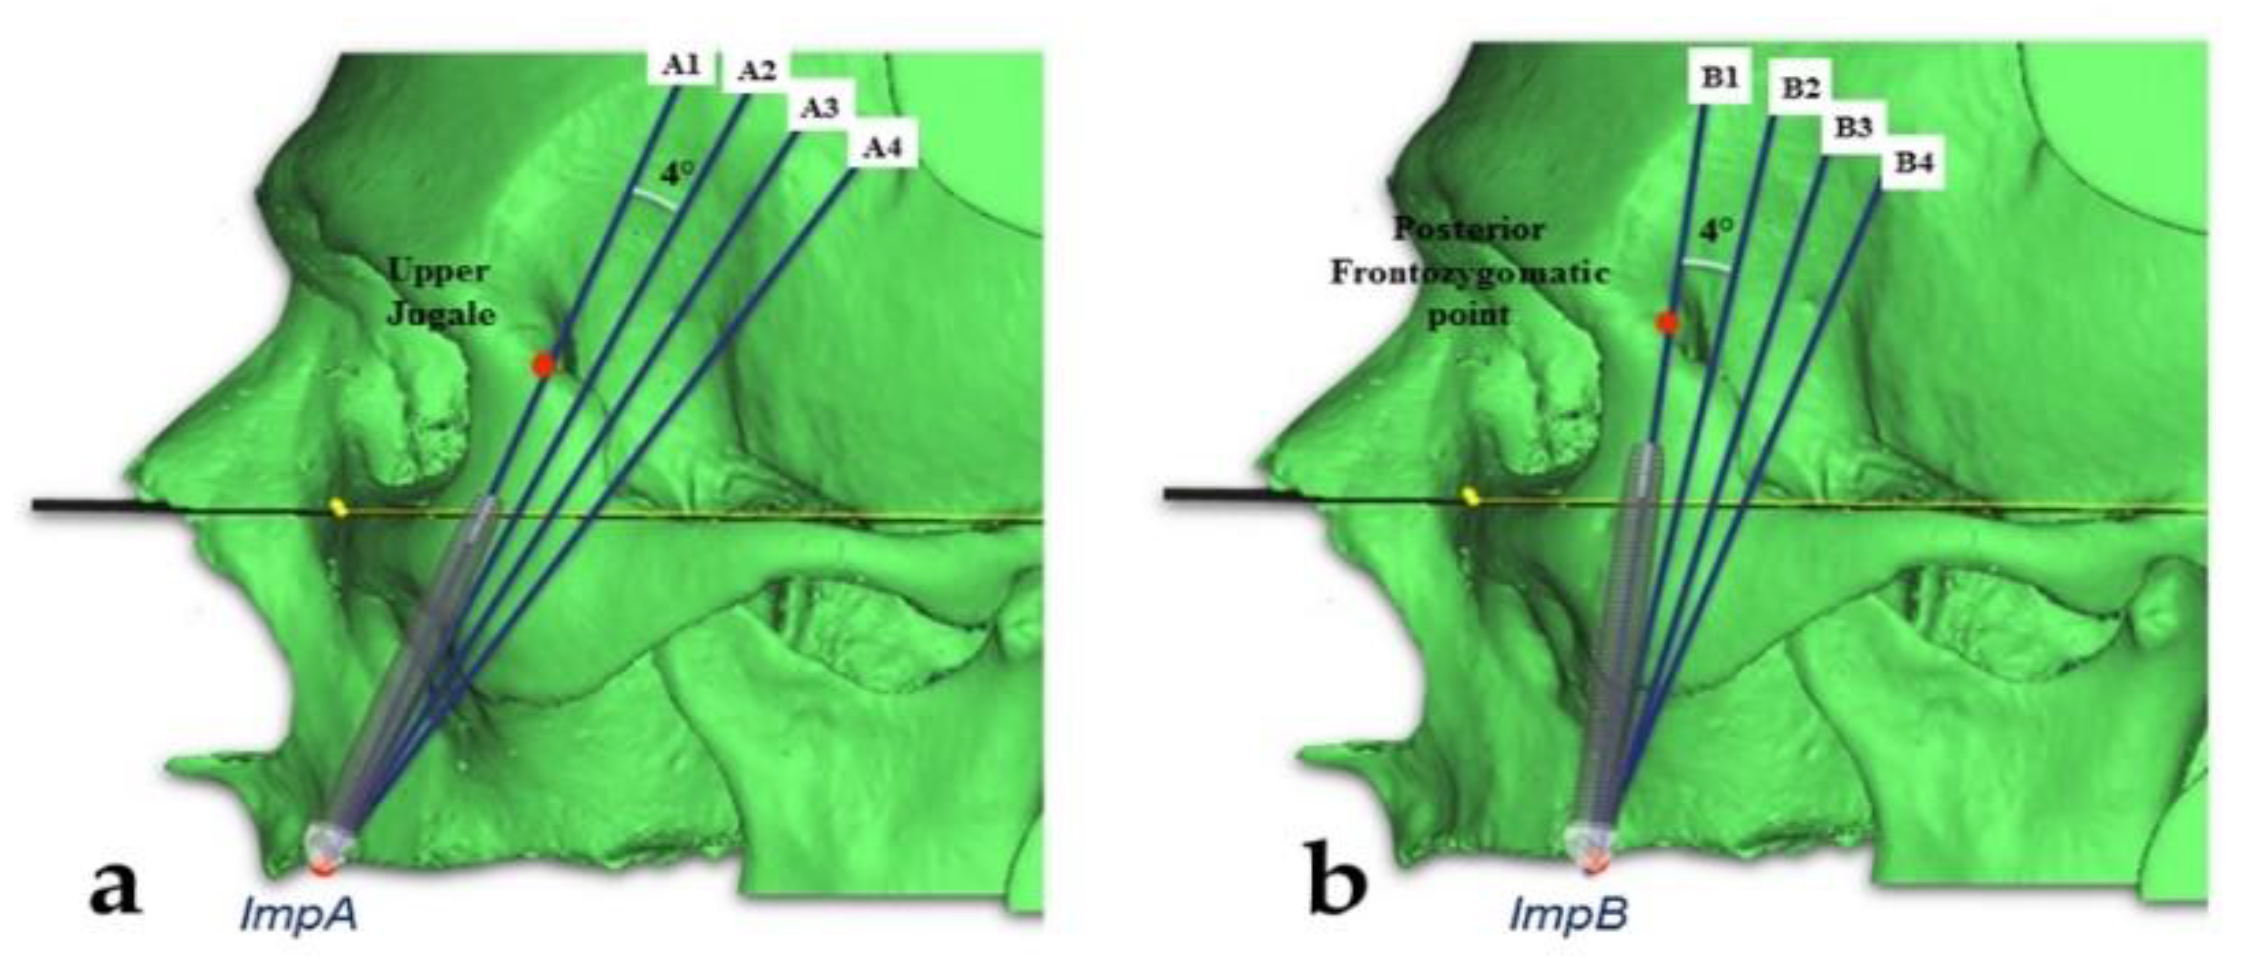

2.3. Measurements of the Zygomatic Bone

- The “upper jugale”: the highest point of the posterior frontal process eminence of the zygomatic bone

- The posterior point of the frontozygomatic suture.Two planes were drawn using the “CAD Objects” tool:

- -

- The “zygomatic anterior” plane, showing the ideal emergence points of prosthetic anterior implants; these were ImpAr/ImpAl and the upper jugale.

- -

- The “zygomatic posterior” plane, showing the ideal emergence points of prosthetic posterior implants; these were ImpBr/ImpBl and the posterior point of the frontozygomatic suture.